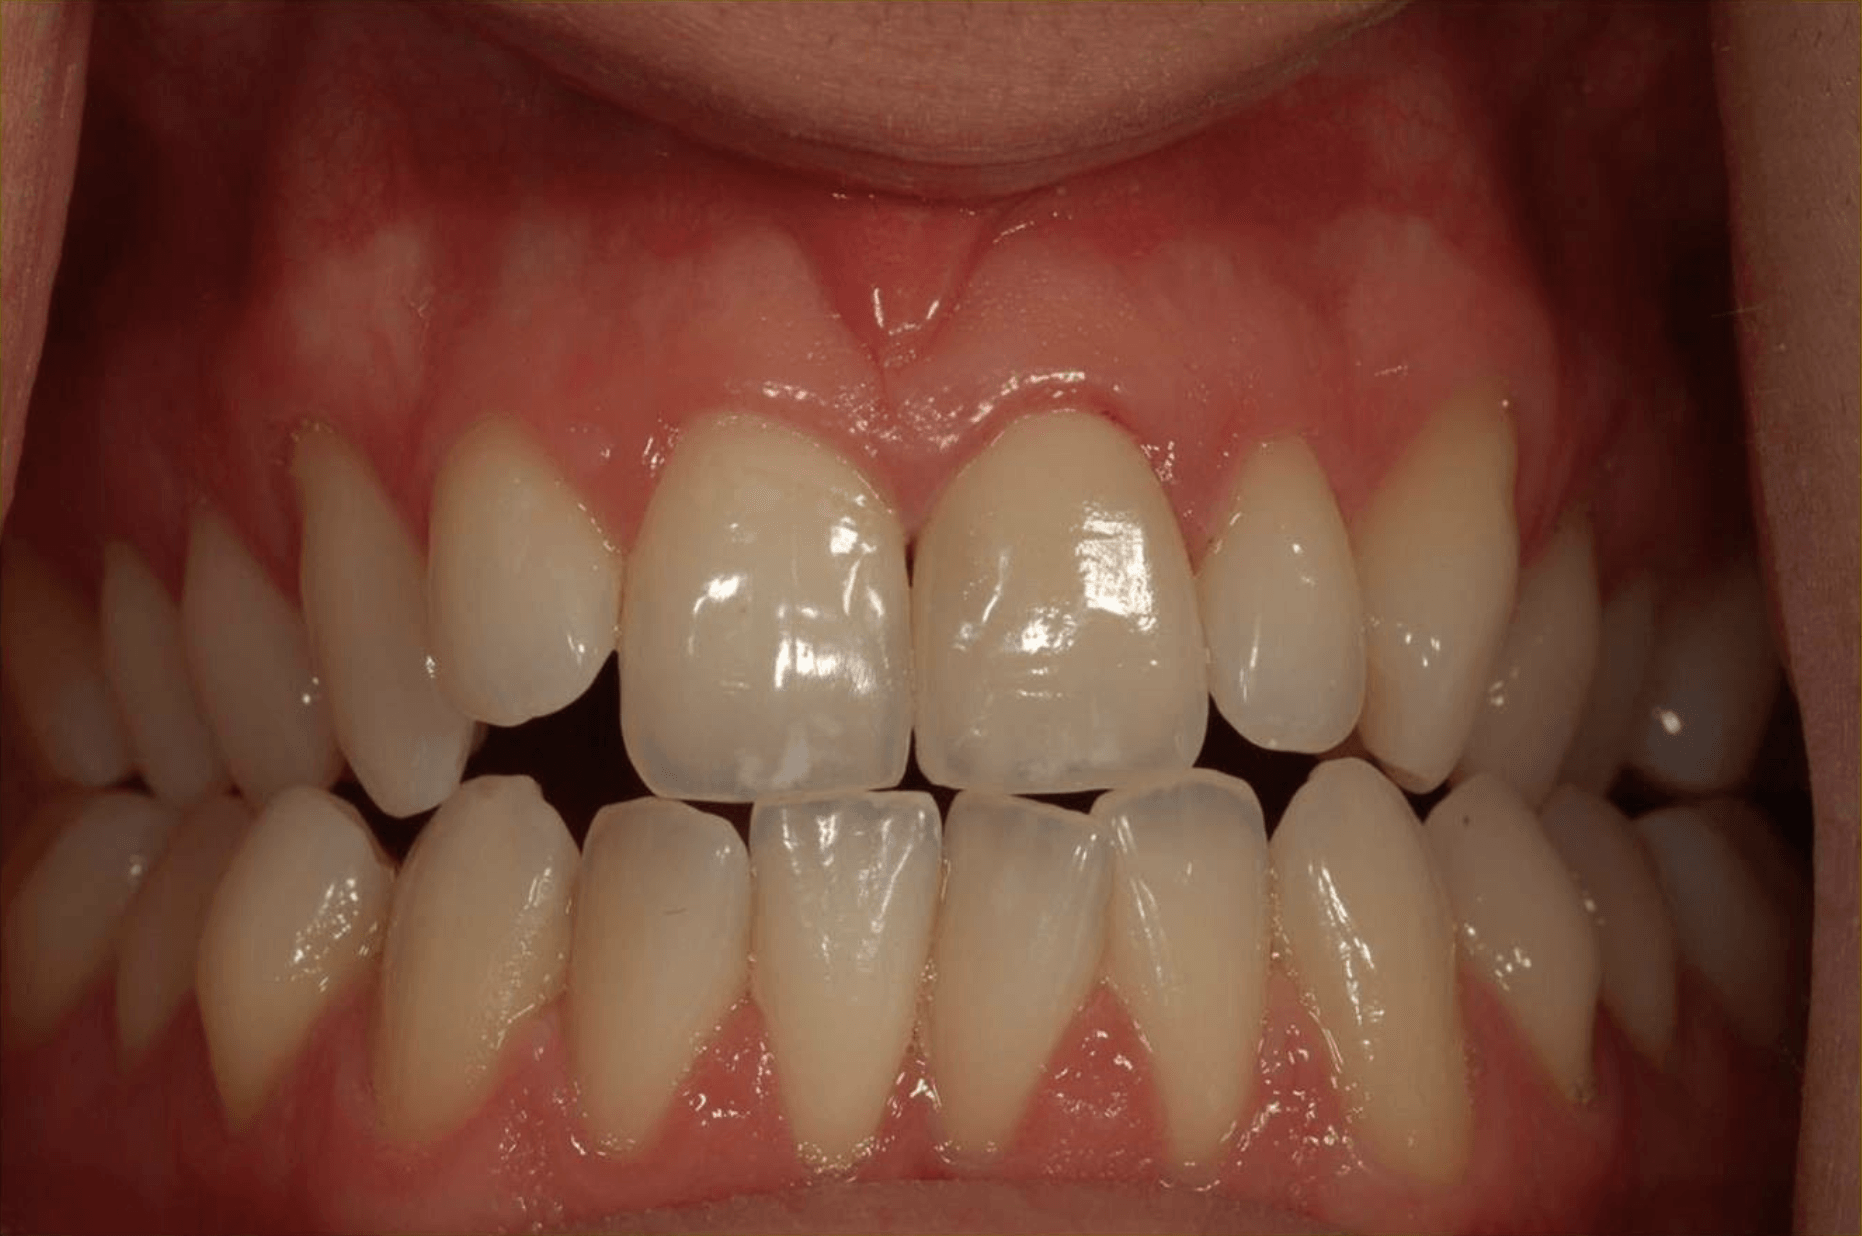

Porcelain Crowns

This patient was unhappy with the short length and discolouration of her teeth. We did a wax up study to evaluate the ideal size and length for her teeth. We then proceeded with six anterior porcelain crowns.